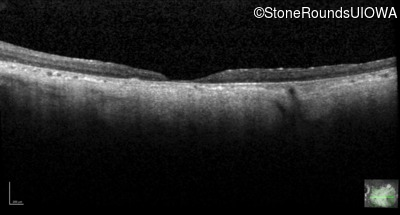

Infrared Fundus Photograph - Left - 10/200 sc

Exemplar